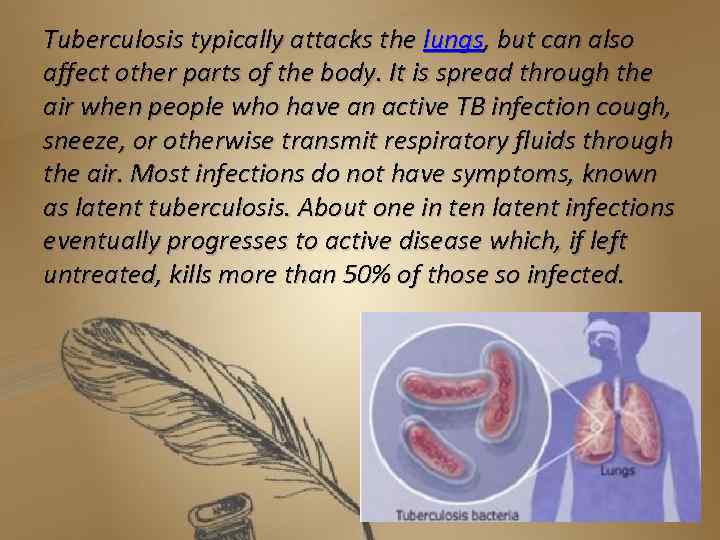

Tuberculosis typically attacks the lungs, but can also affect other parts of the body. It is spread through the air when people who have an active TB infection cough, sneeze, or otherwise transmit respiratory fluids through the air. Most infections do not have symptoms, known as latent tuberculosis. About one in ten latent infections eventually progresses to active disease which, if left untreated, kills more than 50% of those so infected.